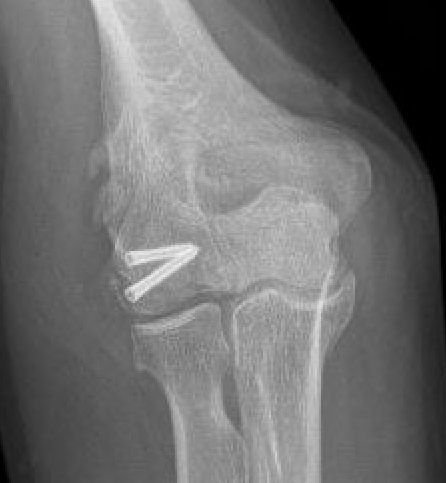

Capitellum fracture with radial head fracture

Concomitant injuries

Radial head

Watts et al JBJS Br 2007

- 79 capitellar fractures

- 24% had a radial head fracture as well